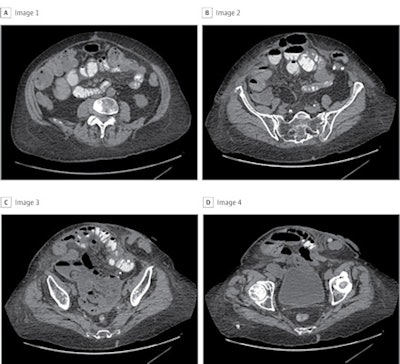

The study included data from 369 patients with ventral hernias who underwent abdominal wall reconstruction but had preoperative CT exams (9,303) between September 2019 and January 2020. Most patients were female (62.9%) and white (87.5%). The deep-learning models were created using an eight-layer convolutional neural network to analyze image characteristics; 80% of the images were used for training and 20% for test sets. The models' performance was compared with six abdominal wall reconstruction surgeons' predictions.